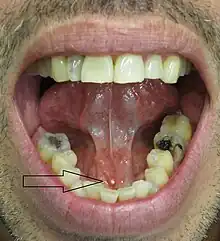

The stone seen in the submandibular duct on the person's right side

Signs and symptoms are variable and depend largely upon whether the obstruction of the duct is complete or partial, and how much resultant pressure is created within the gland.[1] The development of infection in the gland also influences the signs and symptoms.

• Palpable hard lump, if the stone is located near the end of the duct.[1][3] If the stone is near the submandibular duct orifice, the lump may be felt under the tongue.